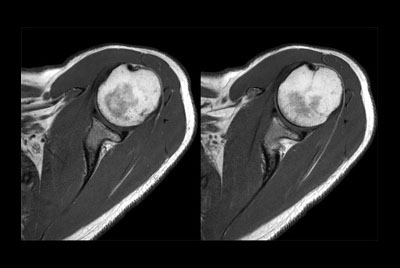

Push-button Shoulder exam, under 5 minutes

Shoulder with oncologic mass

High resolution imaging with the dS 16ch Shoulder coil and Compressed SENSE

Routine shoulder imaging

-

High resolution shoulder imaging

Shoulder with the dS Shoulder 16ch coil

Shoulder imaging

Motion-free MR Arthrogram shoulder imaging

Motion-free Shoulder imaging

Shoulder imaging using ComforTone

Shoulder imaging with dS Flex coil